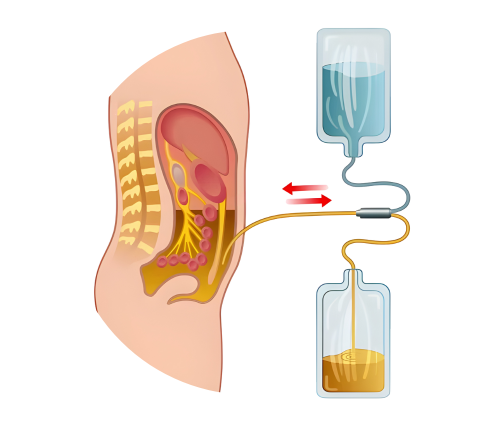

Peritoneal Dialysis

A Gentle, Home-Based Dialysis Option for Kidney Failure Patients

Peritoneal Dialysis (PD) is an effective and patient-friendly treatment option for individuals with Chronic Kidney Disease (CKD Stage 5) or End-Stage Renal Disease (ESRD). Unlike hemodialysis, PD can be performed at home, offering greater flexibility and independence while still effectively removing toxins and excess fluid from the body.